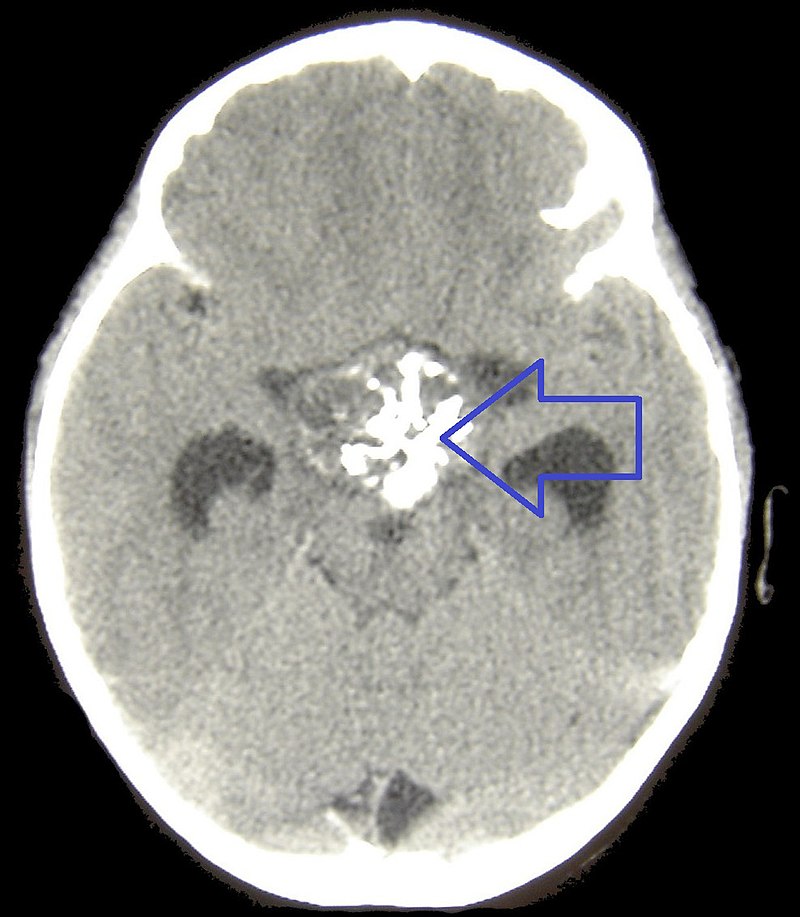

Empty sella syndrome is a rare disorder when the pituitary gland flattens or decreases as a result of problems with the sella turcica’s contents.

Herniation of the arachnoid and cerebral spinal fluid (CSF), otherwise known as cerebrospinal fluid, into the sella turcica compresses and destroys the pituitary gland.

The pituitary gland is “absent” which indicates that the sella turcica is empty on imaging.

• Hypopituitarism

Hypopituitarism. Pituitary Gland Henry Vandyke, Henry Not altered. Public Domain